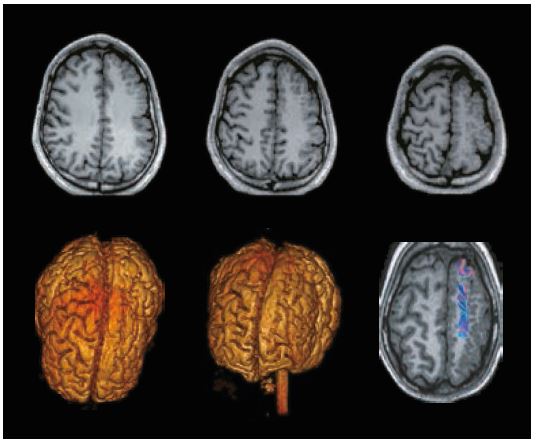

На рисунку 4 показана однобічна лівостороння лобова полімікрогірія у пацієнта чоловічої статі з епілепсією. Осьовий 3D MPRAGE MPR показує багато складок (звивин). Об’ємні зображення показують аномальні звивини.

Рис. 4. Показані невеликі складки на аксіальних зображеннях MPRAGE (угорі), зниклі звивини під час рендерингу об’єму (внизу ліворуч і посередині) та аномальні ділянки волокон білої речовини на DTI (унизу праворуч).

Полімікрогірія характеризується як аномальний розвиток головного мозку до народження, а розвиток дрібних і багатьох складок може бути причиною такого неврологічного розладу, як епілепсія.

ПЕТ-КТ – це одне з обстежень, яке можна виконати для виявлення аномалій перфузії, які можуть свідчити про метаболічні та функціональні аномалії. У цих випадках перфузія ASL є хорошою альтернативою, яка є неінвазивною, не вимагає опромінення та її легко запланувати за стандартним протоколом. На рисунку 4 показано на картах церебрального кровотоку дефекти перфузії на лівій лобовій стороні, які можна співвіднести з аномальними складками в цій області.